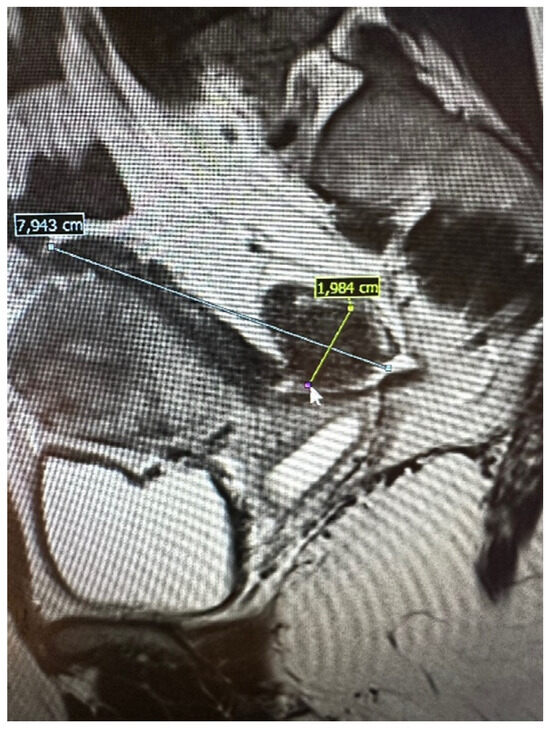

4.4. Ureters’ Assessment (Fu)

4.5. Why Would a Surgeon Use a Score?

- The #ENZIAN classification was invented to meet surgeon needs, and one of its most valuable advantages is its continuous development. Suggestions for future improvements, such as adding the expanded C module or including the ureter and kidney condition, may be considered during the upcoming new edition of “the #ENZIAN app” launch.